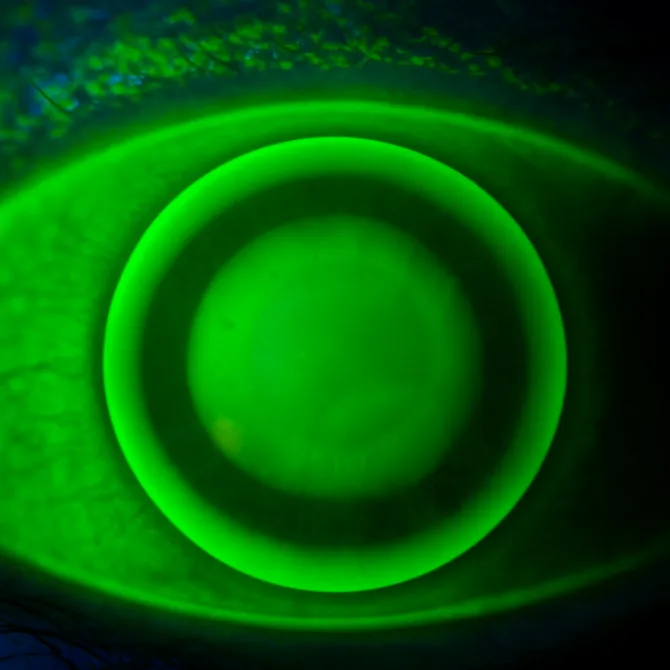

Fluorescein eye image showing contact lens fit and alignment

During a proper contact lens fitting in North York, we evaluate your ocular surface, measure your corneal curvature, and assess tear film quality. That way, you receive lenses optimized for comfort, clarity, and safety.

Specialty lenses for challenging eyes—such as keratoconus, irregular corneas, or post-corneal transplant cases—using rigid gas-permeable or scleral designs.